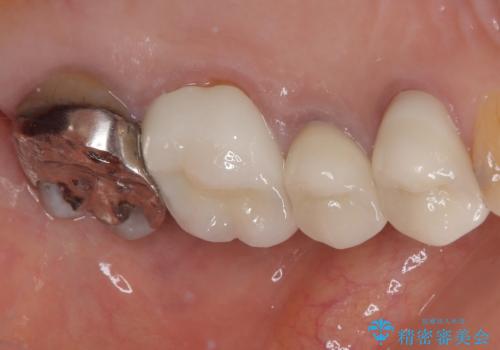

必要な歯に根管治療を行い、オールセラミッククラウンにて補綴治療を行うこととしました。

一部根管治療では症状が改善しなかったため、歯根端切除術を行いました。